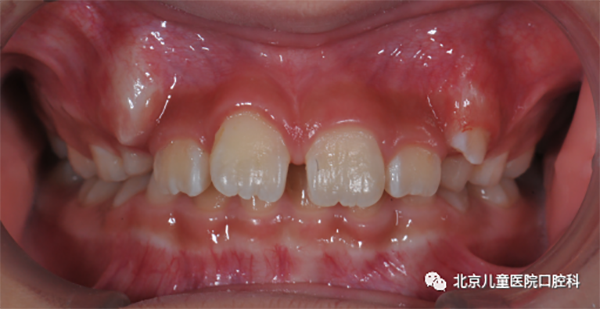

2. 上唇系带位置异常或肥厚

须适时地行唇系带修整术。

图2 上唇系带位置异常